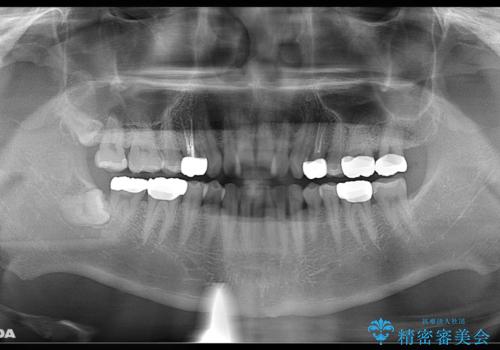

- お口の中にある銀歯を無くしたいとご相談にいらした方です。

適合の良いセラミックにてやり替えを行いました。

元々噛む力が強く、日常的に歯ぎしりもされるとの事でしたので、歯が割れてしまうリスクを軽減させるため、歯全体を覆うクラウンをメインに補綴治療を行いました。

適合不良の補綴物は二次的な虫歯発生のリスクが高まります。

自費診療で用いられる材料は保険適応の材料に比べて、より精密で適合の良い被せ物作ることができるため、長期的な虫歯のリスクを大幅に減らすことが可能です。